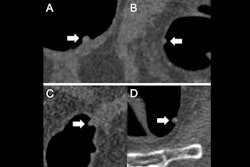

Editor's note: the image used to introduce this article on the homepage is a CTC of a 9-mm polyp (arrow) in the descending colon of a 78-year-old woman. Virtual fly-through 3D reconstructions were used for exact polyp localization. Courtesy of Dr. Sergio Grosu and colleagues from Ludwig Maximilian University of Munich and the RSNA.